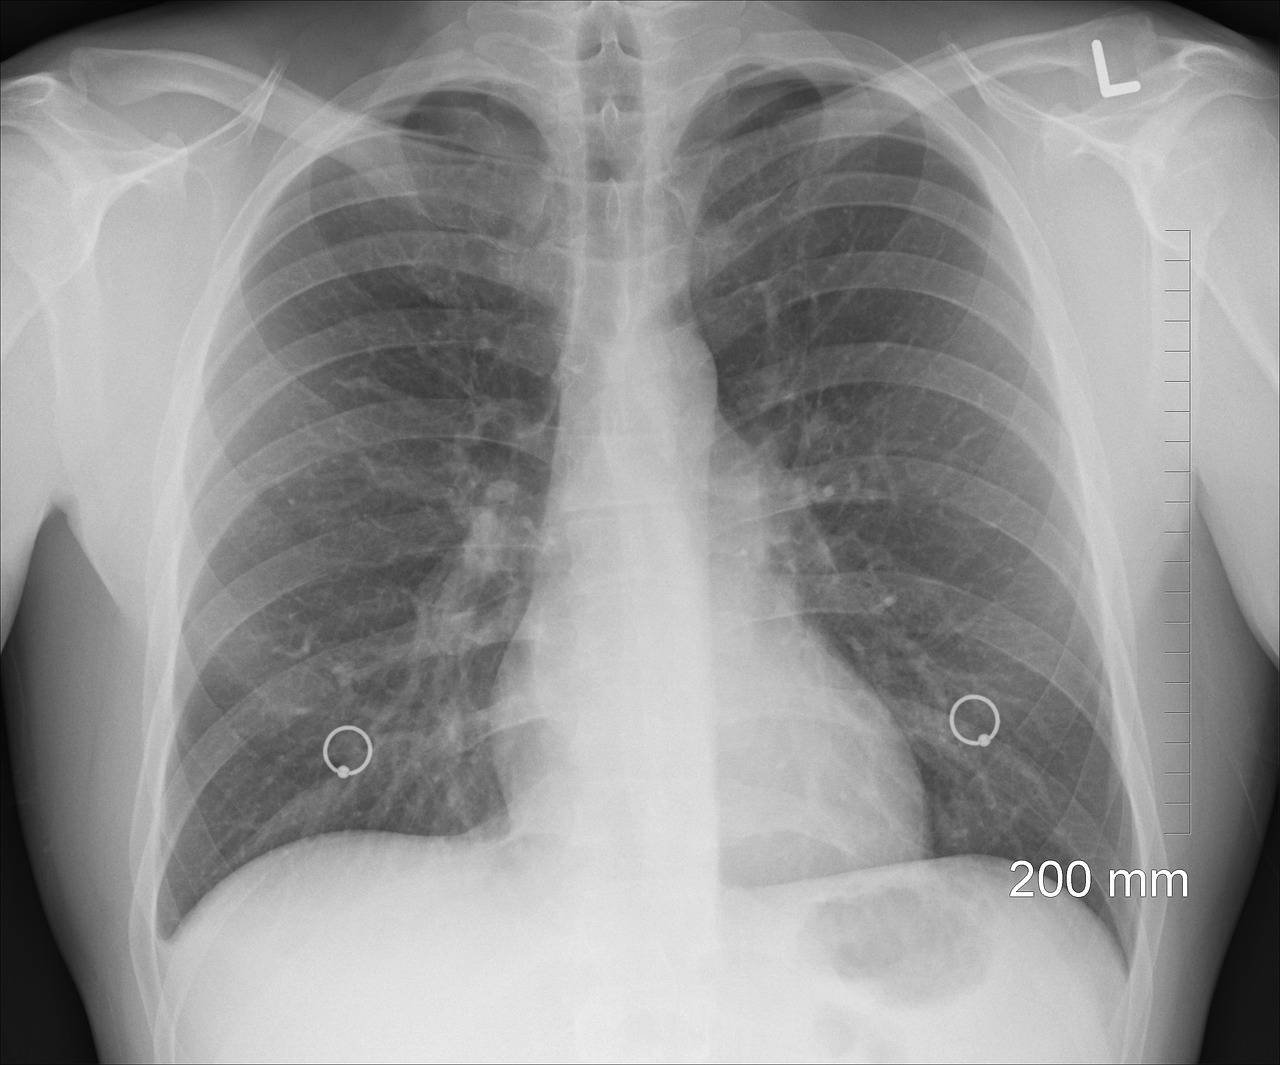

I polmoni sono due organi spugnosi e leggeri, situati nel torace e protetti dalla gabbia toracica. Hanno una forma conica, con una base più ampia che poggia sul diaframma e un apice più stretto che si trova vicino alla clavicola.

• Polmone destro → più grande, diviso in tre lobi (superiore, medio, inferiore).

• Polmone sinistro → più piccolo, diviso in due lobi (superiore e inferiore) per fare spazio al cuore.

I polmoni sono avvolti da una sottile membrana chiamata pleura, che riduce l’attrito durante la respirazione.